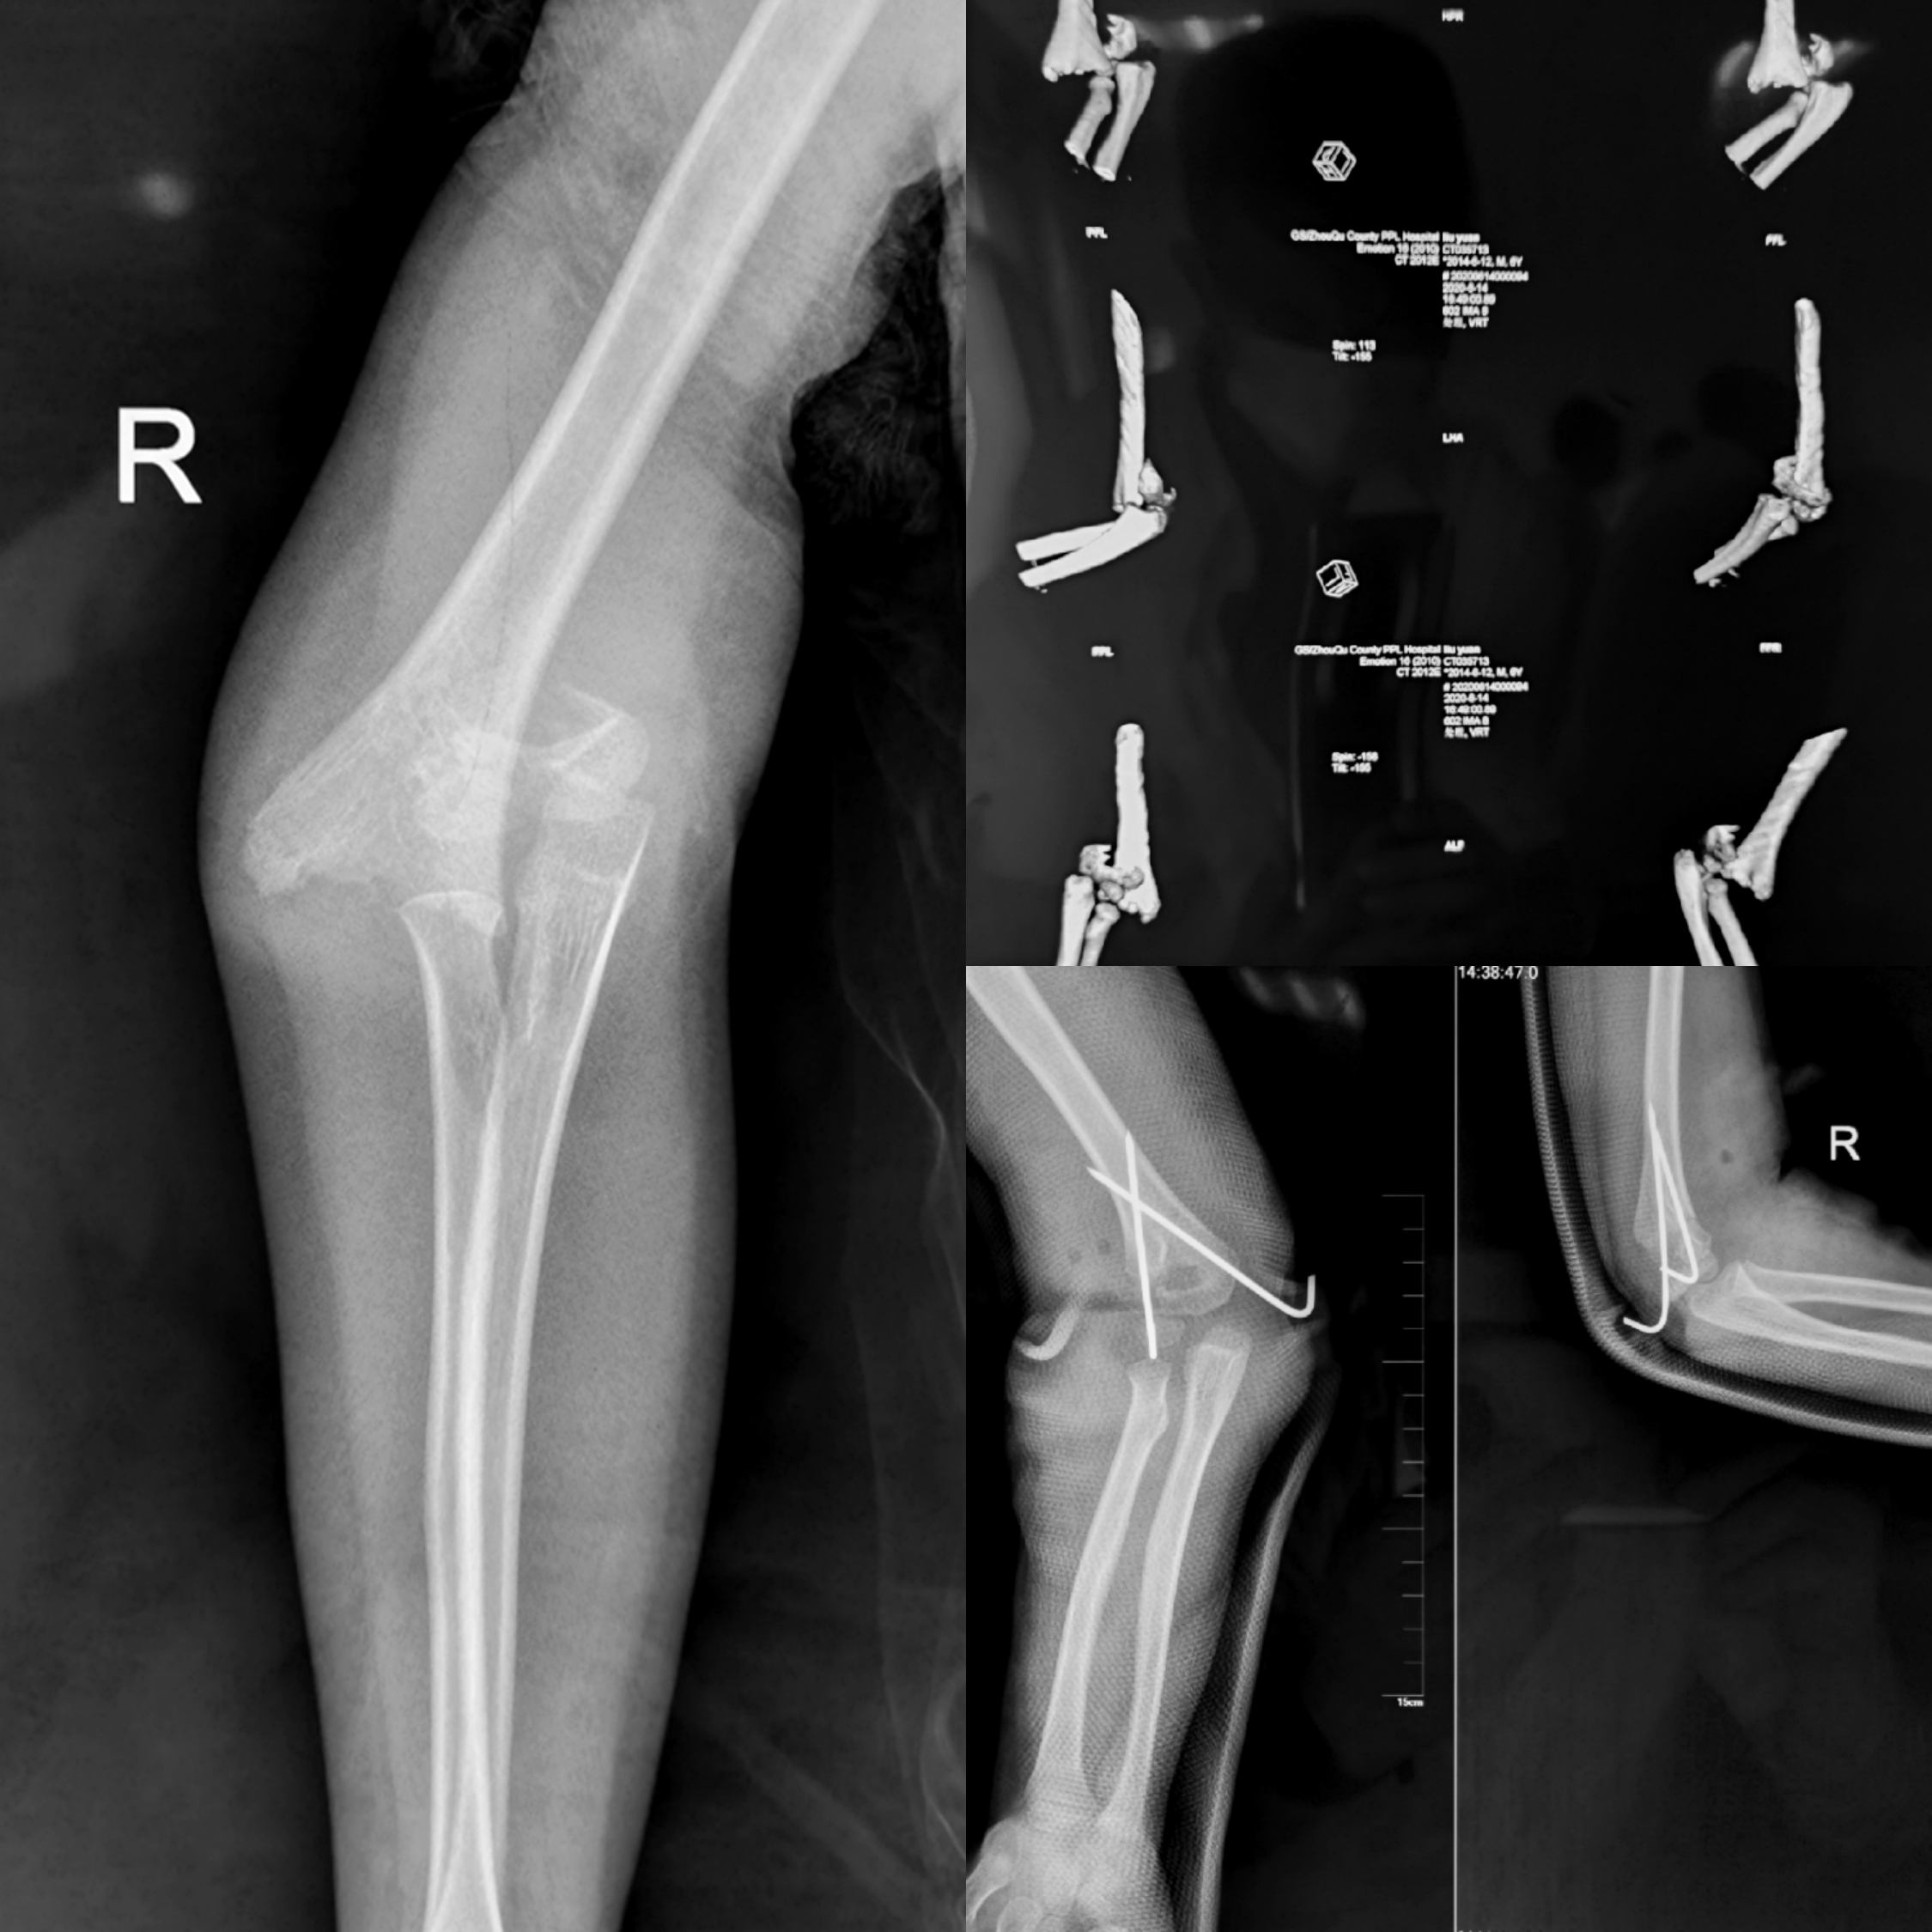

患儿,男性,6岁。以“玩耍时摔倒致右肘关节肿痛伴活动受限1天”入院。入院诊断显示右肱骨髁上骨折(Gartland Ⅲ型)。入院查体发现患儿右肘关节呈“靴状畸形”,肘关节周围肿胀明显,可见明显的皮下淤青,压痛(+),右肘关节屈伸活动均明显受限,右手腕关节及手部各关节活动良好,末梢血运及感觉无异常。患肢X线片提示右肱骨髁上骨折(Gartland Ⅲ型)。经严格的病情评估和术前讨论后,6月17日,在陈永刚医师的指导下,舟曲县人民医院骨科团队顺利完成“右肱骨髁上骨折经肘内侧切口切开复位内固定术”。术中一切顺利,术后患儿恢复良好。